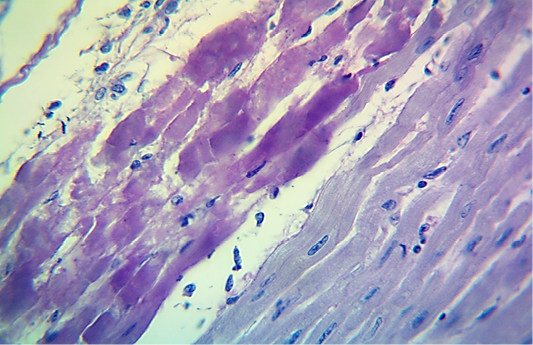

Microscopic image of calf’s heart (“tiger-heart”) from a calf that died from an acute form of FMD, showing severely affected muscle fibers with coagulative necrosis that stained magenta in color (arrow), with infiltration of lymphocytes (arrowhead). (PAS stain, 600x).